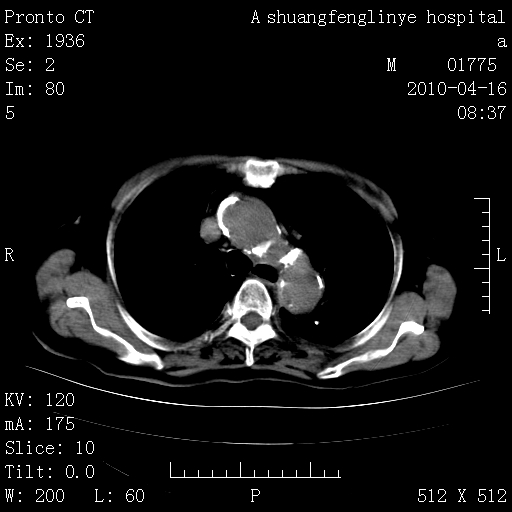

标题: CT25784:咳痰、请会诊!结核? [打印本页]

标题: CT25784:咳痰、请会诊!结核?

陈旧性结核,胃腔扩大,脾脏受压后移

慢支肺气肿,左上陈旧性结核,主动脉冠脉钙化

典型 夹层动脉瘤。 内膜瓣钙化移位

1)左肺上叶结核(纤维、增殖病灶)。2)冠状动脉及主动脉钙化。

1)左肺上叶结核(纤维、增殖病灶)。2)冠状动脉及主动脉钙化。肺动脉高压